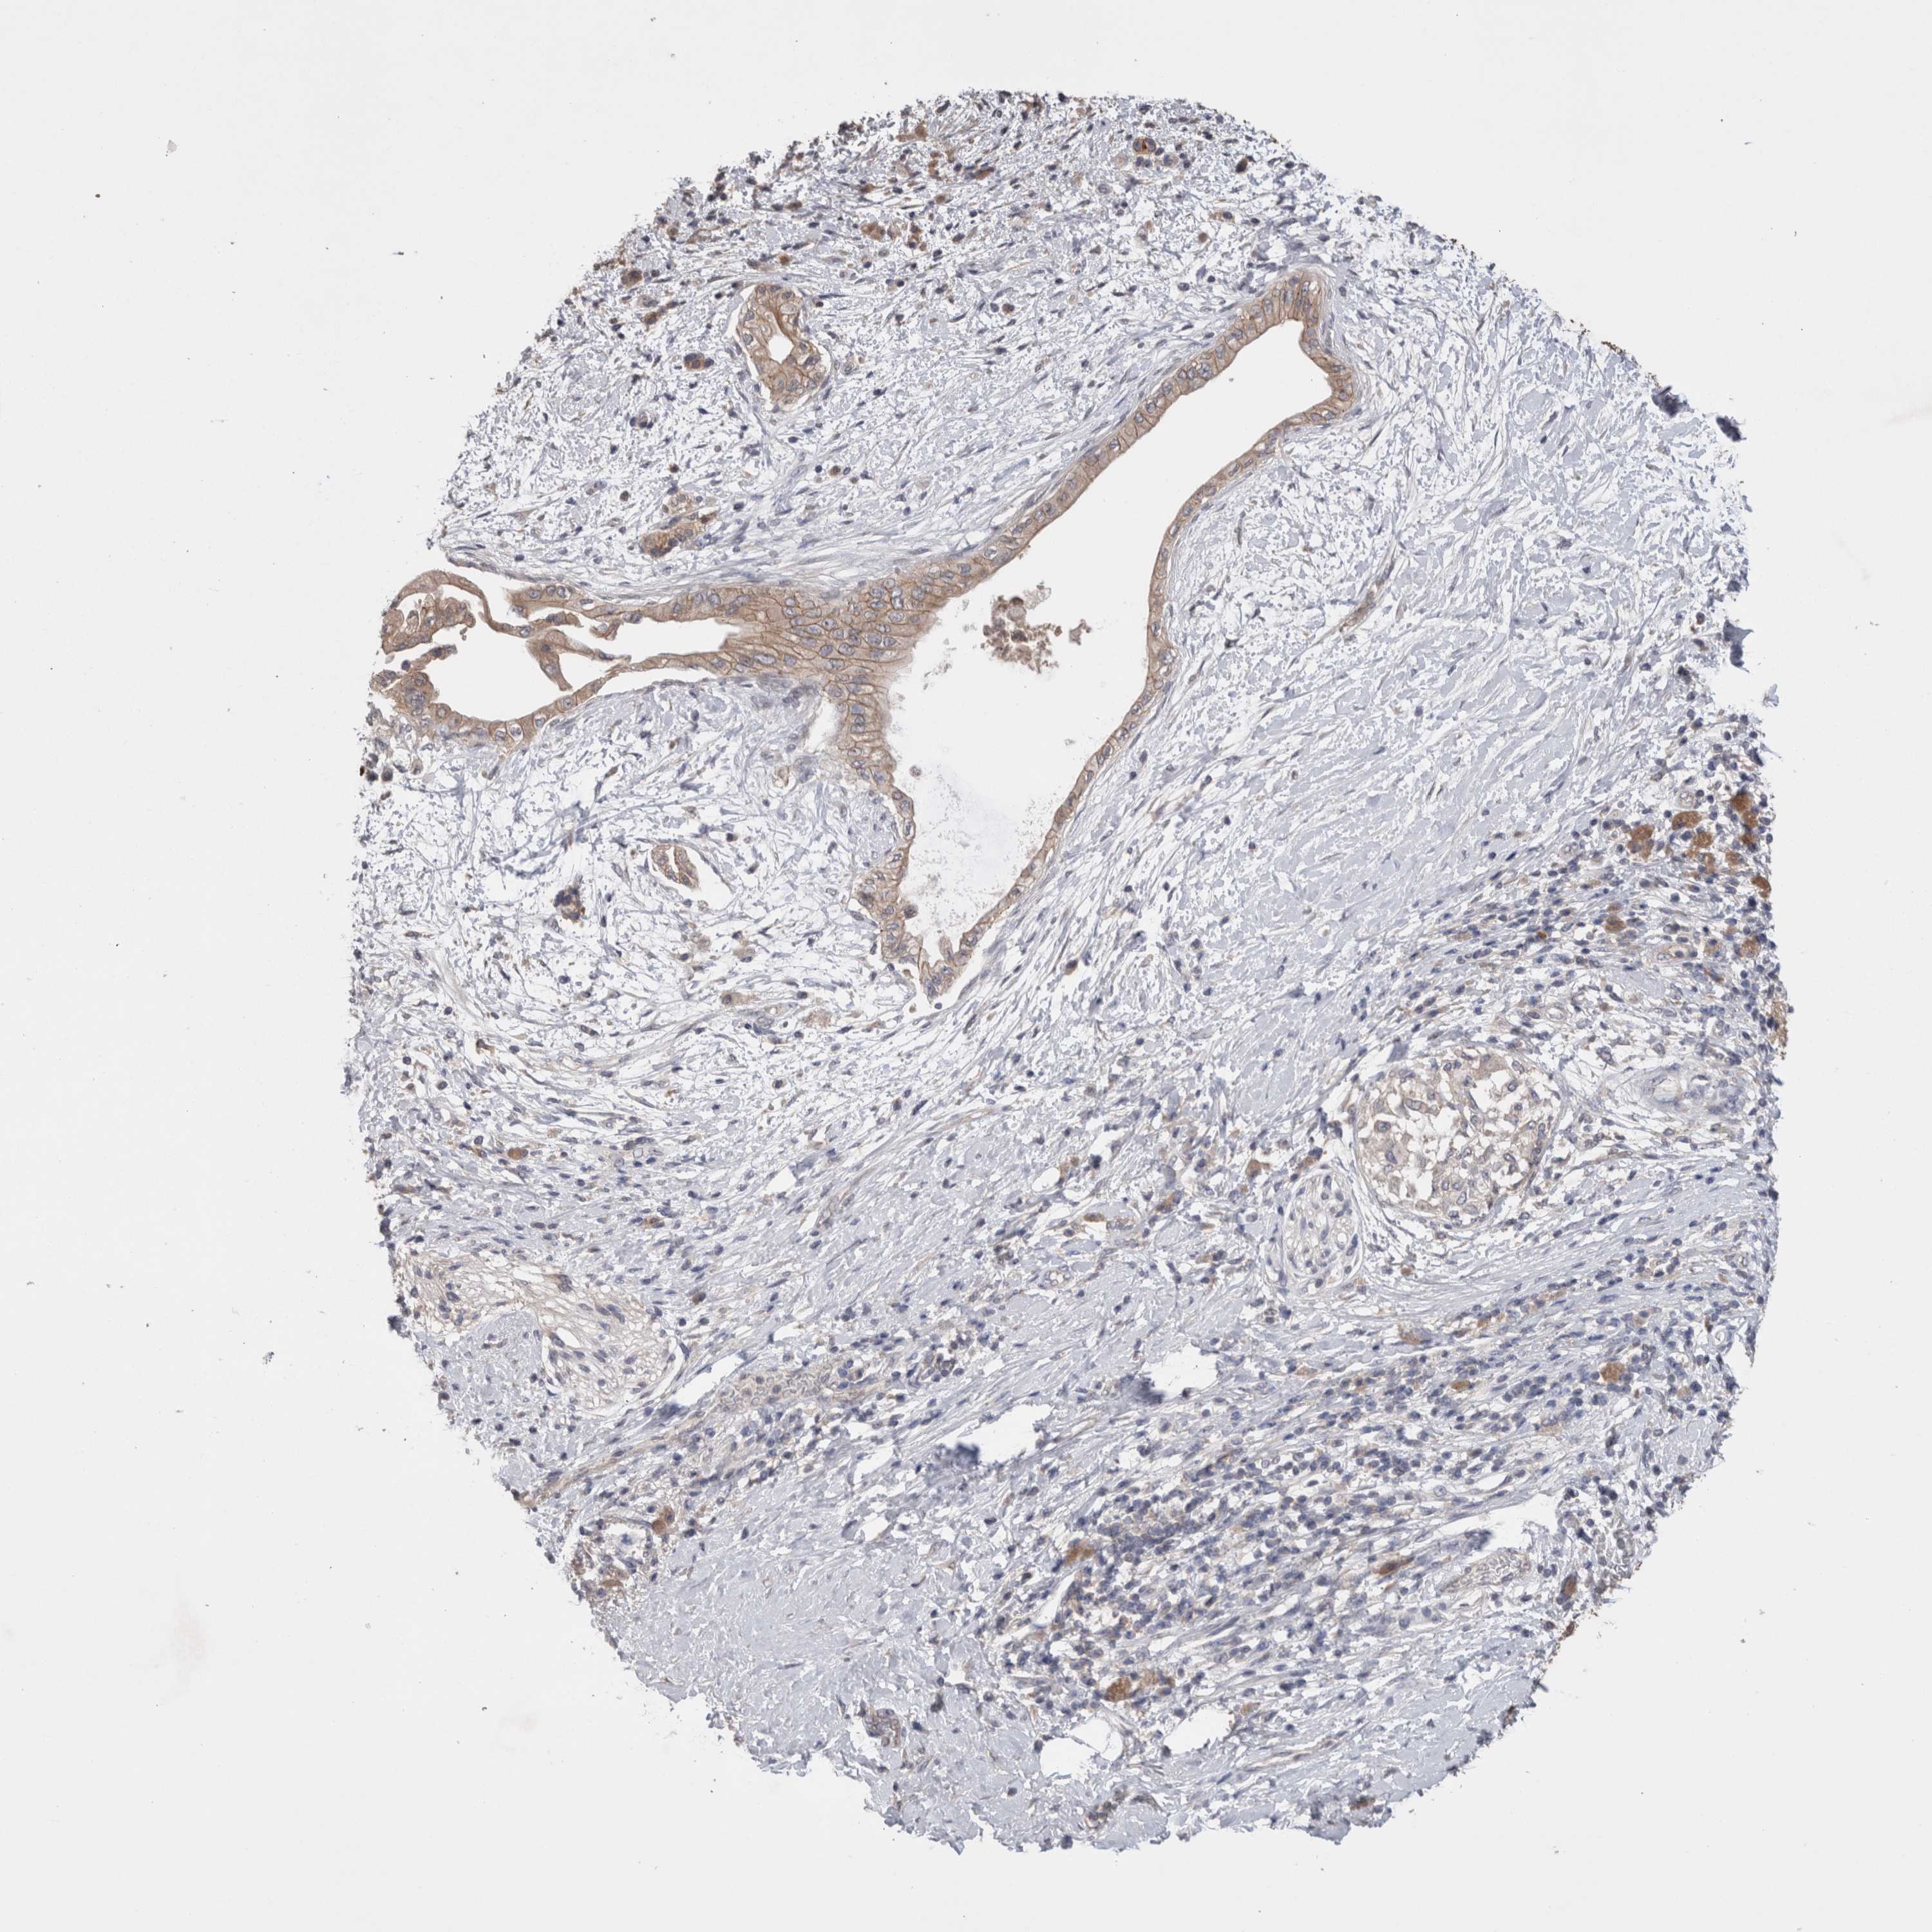

PANCREATIC CANCER - Protein expressioni

A mouse-over function shows sample information and annotation data. Click on an image to view it in a full screen mode. Samples can be filtered based on level of antibody staining by selecting one or several of the following categories: high, medium, low and not detected. The assay and annotation is described here.

Note that samples used for immunohistochemistry by the Human Protein Atlas do not correspond to samples in the TCGA dataset.

Antibody stainingi

Antibody staining in the annotated cell types in the current human tissue is reported as not detected, low, medium, or high, based on conventional immunohistochemistry profiling in selected tissues. This score is based on the combination of the staining intensity and fraction of stained cells.

Each image is clickable and will lead to virtual microscopy that enables deeper exploration of all samples and also displays staining intensity scores, fraction scores and subcellular localization as well as patient and tissue information for each sample.

Antibody HPA024335

Staining

High

Medium

Low

Not detected

Intensity

Strong

Moderate

Weak

Negative

Quantity

>75%

75%-25%

<25%

None

Location

Nuclear

Cytoplasmic/membranous

Cytoplasmic/membranous,nuclear

Adenocarcinoma, NOS